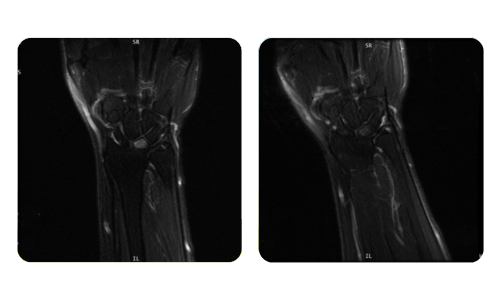

Der Fortschritt unserer Patienten, gemessen vor und nach der hyperbaren Therapie, spiegelt die Effizienz und die positive Wirkung der Behandlung wider. Entdecken Sie dokumentierte Ergebnisse der hyperbaren Therapie in der Klinik Hyperbarium Oradea, basierend auf klinischen Bewertungen und objektiven Daten, die signifikante Verbesserungen bei verschiedenen Erkrankungen belegen.